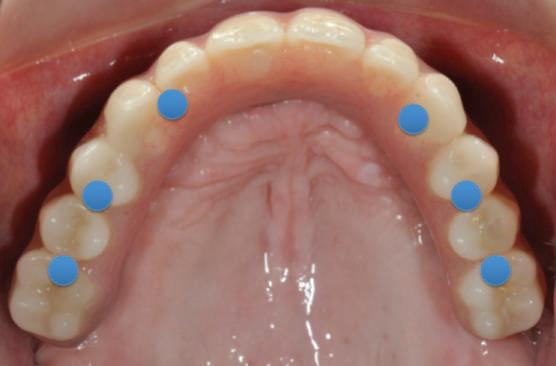

Reprepararea intraorală a bonturilor Acest pacient prezenta dentiţia maxilară compromisă, refuzând proteza mobilizabilă. Prin abordarea în etape, se menţin o parte din bonturile dentare naturale; s-a observat recesie în momentul amprentării pentru cel de-al doilea grup de implanturi.

Fig. 1 prezintă pacientul după inserarea primului set de bonturi implantare individualizate; dinţii naturali adiacenţi

sunt încă prezenţi pentru a susţine puntea provizorie.

Şapte luni mai târziu (fig. 2), acele bonturi individualizate din prima etapă au manifestat semne de recesie de 1-3mm. Atitudine: S-a decis reprepararea intraorală a tuturor bonturilor (fig. 3), astfel încât toate marginile bonturilor să fie la nivelul sau sub marginea gingivală (de notat că 1.1. şi 2.1. au fost submersaţi ulterior pentru a avea sprijin implantar deplin).

Deşi reprepararea a îmbunătăţit marcat estetica finală, a necesitat aplicarea şnurului de retracţie, amprente noi şi turnări noi.

Un caz separat dar similar ilustrează în figurile 4 și 5 reprepararea intraorală a bontului.

Cazul (1): Reprepararea intraorală a bonturilor Figurile

1. Aspect după inserarea primului set de bonturi implantare individualizate.

2. După 7 luni, bonturile individualizate din prima etapă au prezentat recesie de 1-3mm.

3. Bonturile repreparate intraoral.

Alt caz (1) Figurile

4. După osteointegrarea implantului 2.4., s-a observat recesia în etapa de amprentare a implantului 2.5.; s-a decis reprepararea marginilor bontului individualizat CAD/CAM 2.4. Înainte de preparare s-a aplicat şnur de retracţie pentru a evita lezarea ţesutului şi a îmbunătăţi vizibilitatea dintelui 2.3. şi a marginii bontului implantar individualizat. Aşa cum era de aşteptat, recesia a fost mai mare de-a lungul versantului distal al bontului 2.4. adiacent locului de extracţie vindecat/cu implantul mai nou.

5. Bontul individualizat aplicat (2.5.) cu bontul repreparat anterior (2.4.). Nu a survenit recesie nouă de o perioadă de peste 3 ani.